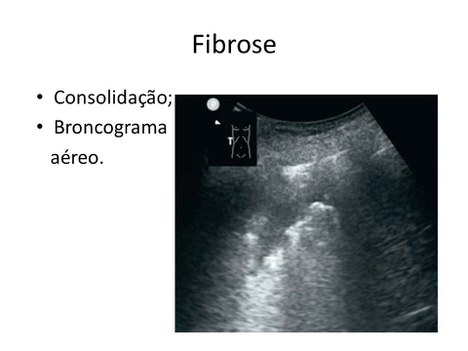

Imagem de ultrassom mostra marcas em pulmão com fibrose causada pelo coronavírus (Divulgação)

O processo pretende ser ágil. Por ele um técnico faz as imagens com o ultrassom portátil e, pelo próprio telefone manda, via internet, para uma central. Wagner Coelho fala sobre a medicina a distância: “É isso que se chama de telemedicina. Os dados são coletados num lugar em que não tem a infraestrutura e manda para um centro que reúne essas informações. Em seguida alguém decide sobre o paciente que está  longe”. Ao final, um banco de dados é preparado para classificar cada tipo de mancha. Desse modo o sistema saberá o que cada uma delas quer dizer. Isso permite, inclusive, o acompanhamento do paciente.

Bolsista da CAPES, Fellipe Allevato, fisioterapeuta e doutorando em Ultrassonografia Pulmonar, trabalha no projeto e explica que, apesar de ser muito usado como meio de diagnóstico de síndromes respiratórias, nem todos os elementos que surgem na imagem de ultrassonografia do pulmão são plenamente entendidos pela literatura científica. “Minha expectativa é gerar um material que simule os principais tipos de imagem de doença pulmonar com ultrassonografia para que, no atendimento de emergência, profissionais que não usem habitualmente o ultrassom na prática possam fazer o diagnóstico específico para essas doenças”, encerra Allevato.